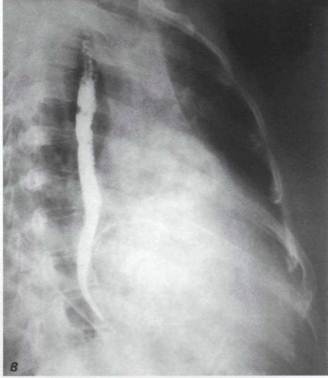

Правая (первая) косая проекция

При митральной недостаточности, в отличие от митрального стеноза, в правой передней косой проекции нет резкого расширения дуги конус пульмоналис и между передним контуром сердца и реберной границей остается свободным широкое клиновидное пространство. При митральной недостаточности контрастированный пищевод в правом переднем косом положении отклоняется кзади по дуге большого радиуса (рис. 35). Из-за резкого увеличения левого предсердия и атрофических изменений клетчатки средостения пищевод приобретает чрезмерную подвижность. При этом в течение одной рентгеноскопии он может изменять свое положение. Это явление носит название «соскальзывания» пищевода с левого предсердия.

Отклонение контрастированного пищевода при митральной недостаточности в правой косой проекции

При выраженной митральной недостаточности увеличено левое предсердие, что еще более четко выявляется в косых положениях с одновременный приемом бария. В отличие от митрального стеноза, пищевод отклоняется кзади предсердием по дуге большого радиуса (8- 10 см).